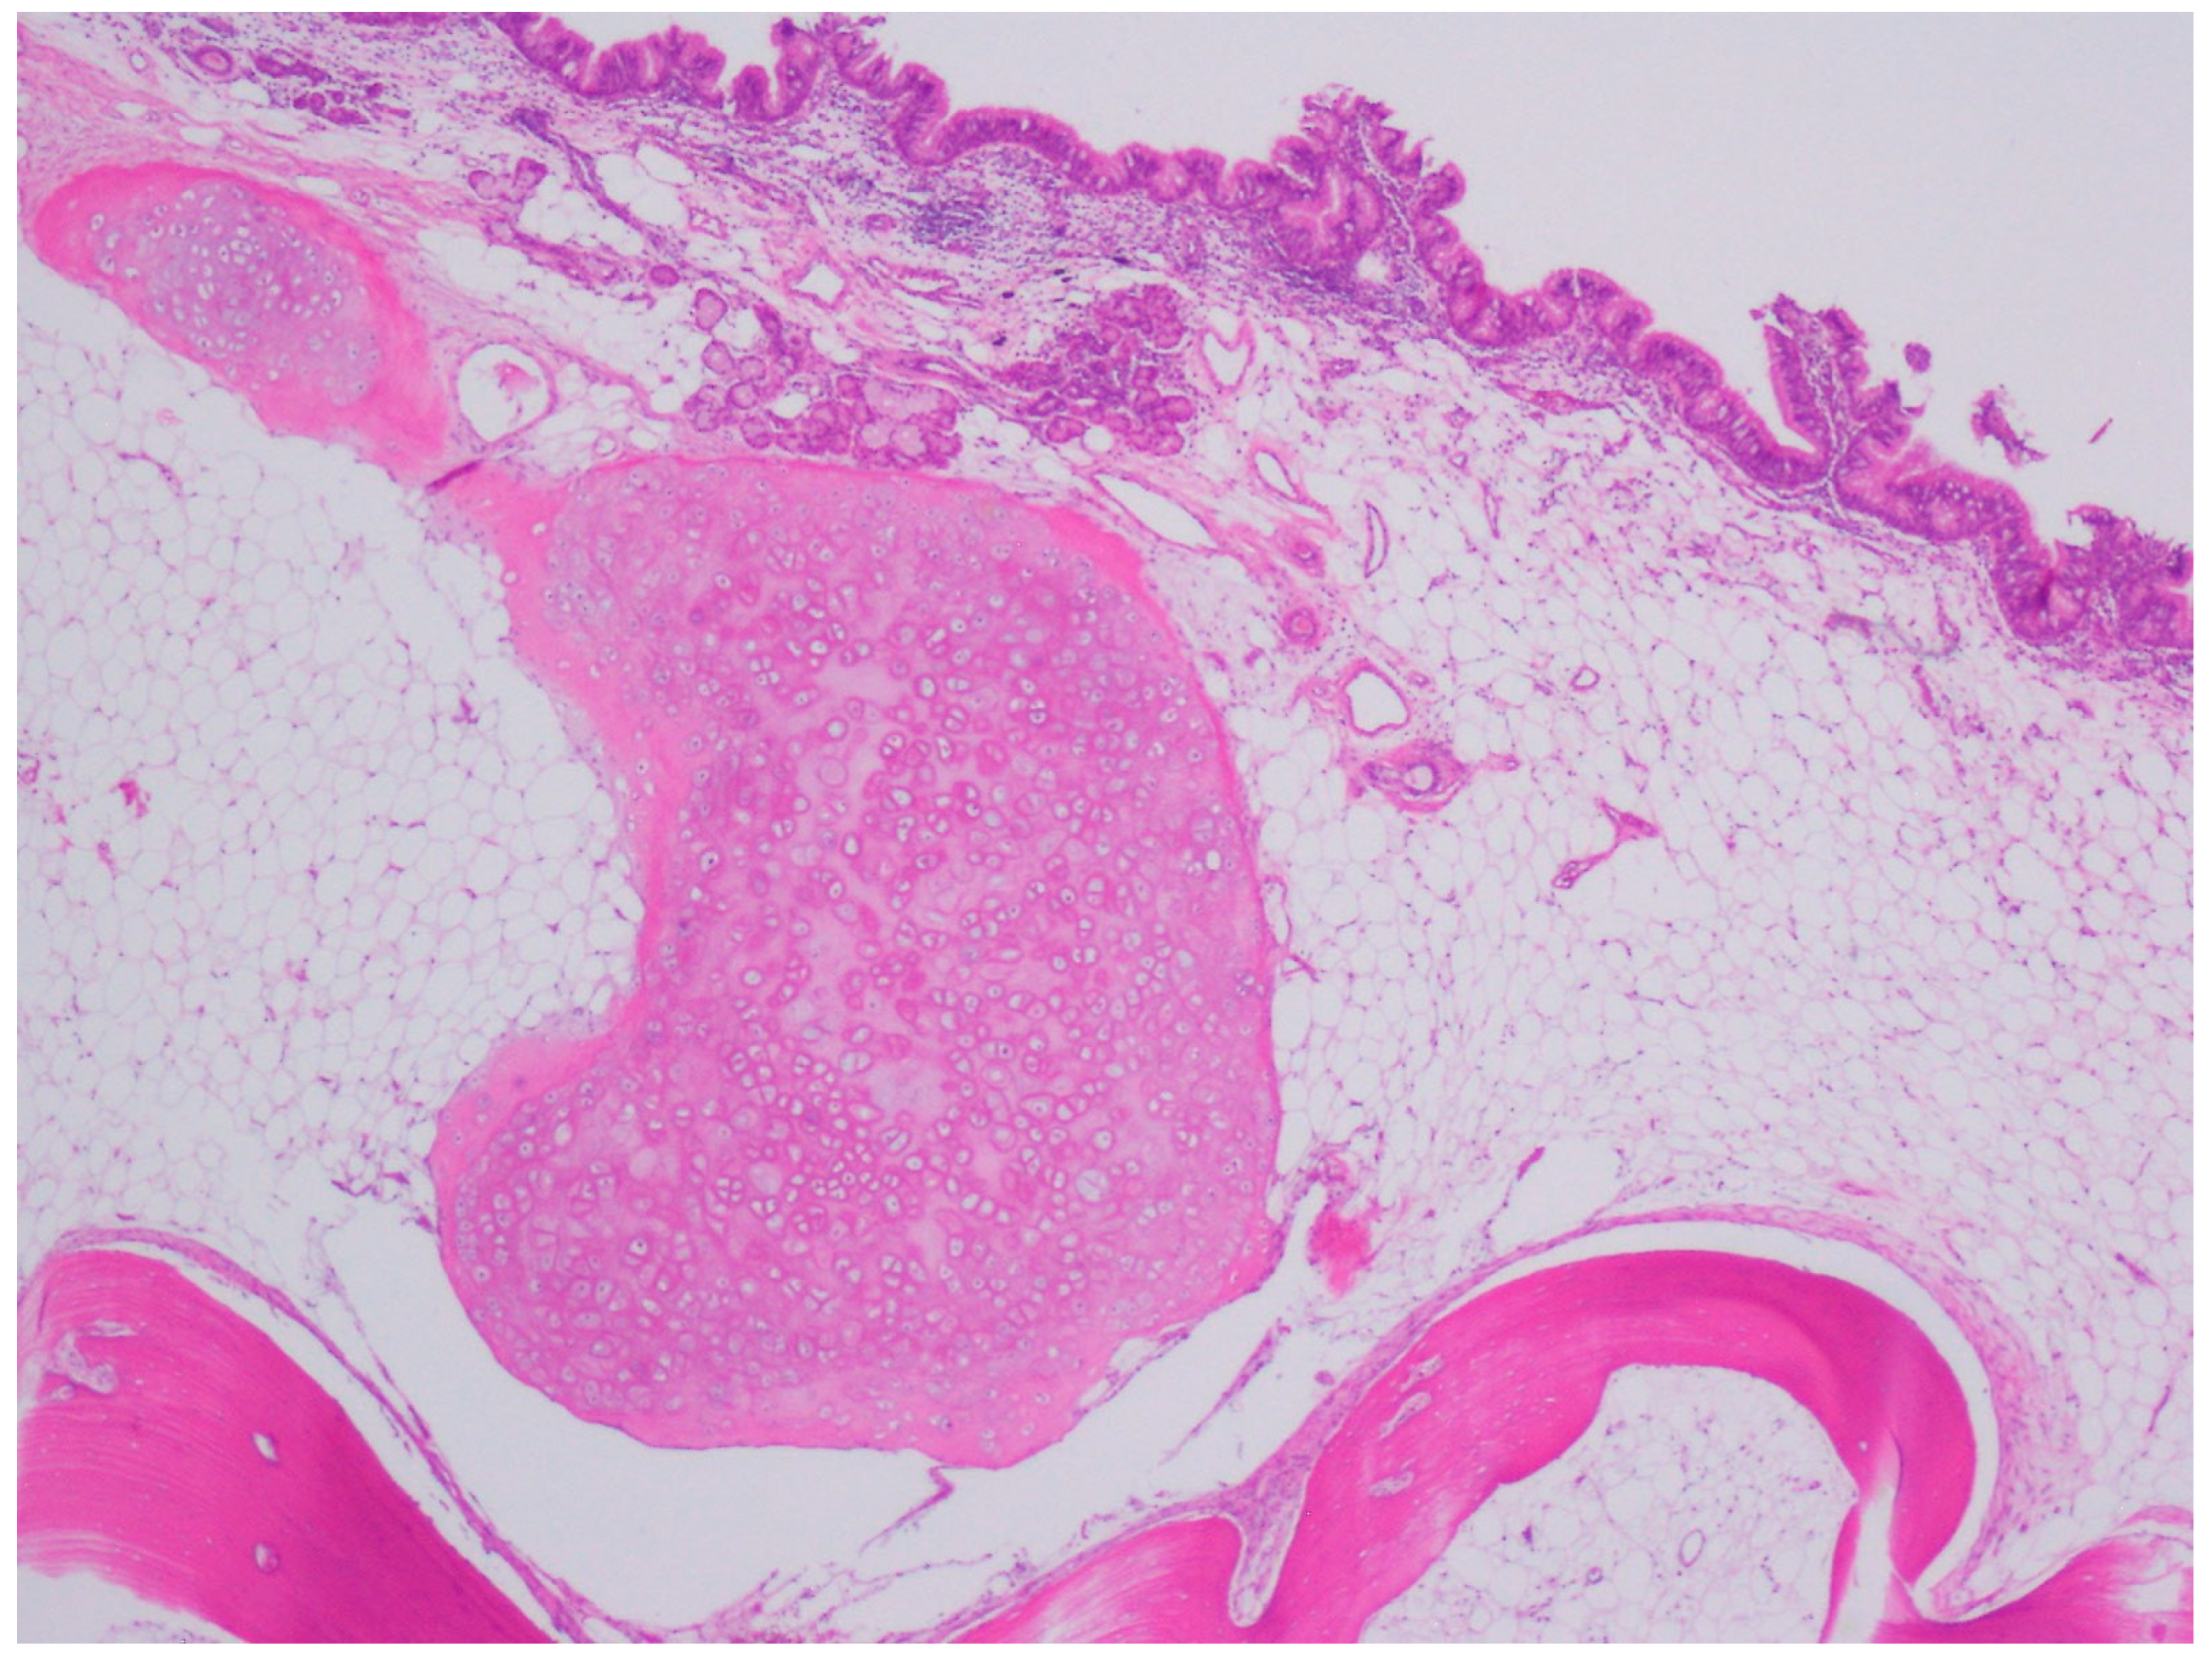

A Rare Case of a Large Composite Endometrioma–Mature Cystic Teratoma: The Importance of Surgical Treatment and Pathologic Diagnosis

2. Case Presentation